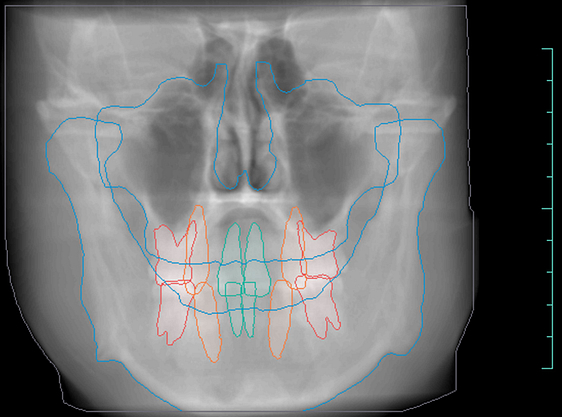

Orthodontic Report

Diagnocat is also capable of generating orthodontic reports.

This requires a CBCT radiograph with a minimum field of view of 13 x 15 x 15cm. Our Kavo OP3D machine achieves this by taking a double-field exposure and stacking two exposures on top of each other.

Diagnocat generates OPG and frontal and lateral cephalometric reconstructions from the CBCT data.

Tracings of the maxilla, mandible, central incisors, canines and molars. All automatically.

Cross-sectional and coronal views of teeth show torque and buccolingual relationships such as crossbite.

TMJ coronal/sagittal slices and summations visualize abnormal positioning/shape of the mandibular condyle.